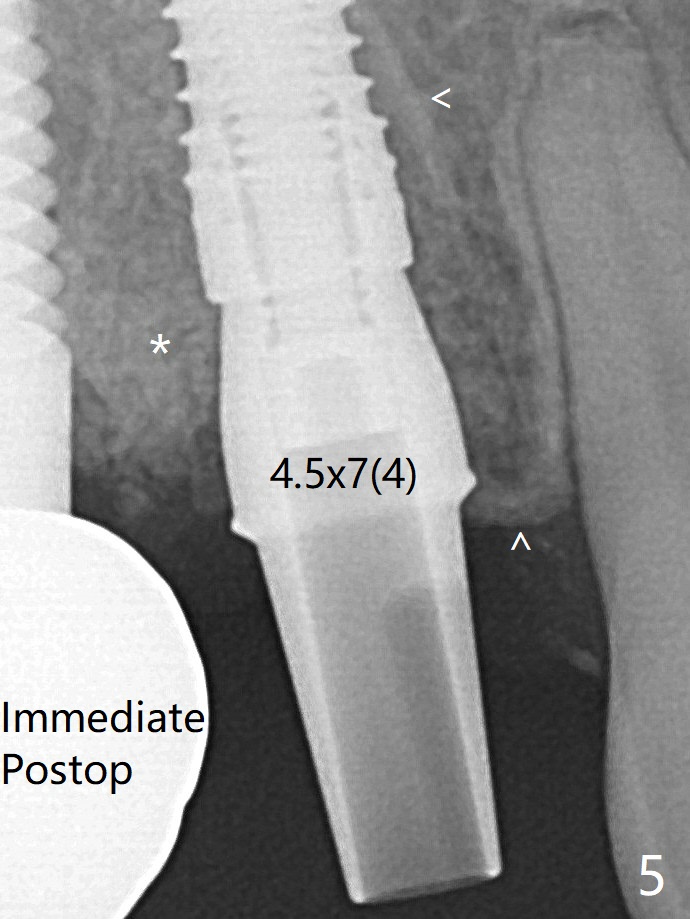

Immediate postop, the abutment margin appears to be subcrestal (biologic width violation, Fig.5).  The gingiva bleeds easily when the provisional is removed 2 weeks and 3.5 months postop.  It is difficult to insert gingival retraction cords.  When an abutment with longer cuff is placed, the packing is easier (Fig.7 (^: resorbed mesial crest)).  *: bone graft.  The mesial socket gap (Fig.5: <) disappears 3.5 months postop (Fig.7).